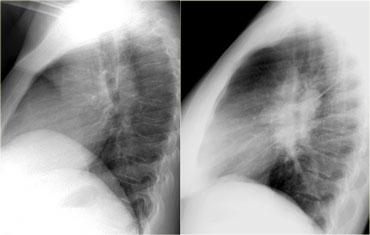

Bên trái là hình ảnh của hai bệnh nhân khác nhau.

Hãy mô tả các dấu hiệu và tiếp tục.

Trên phim X-quang bên trái, có một tổn thương tạo góc nhọn với trung thất.

Đây phải là một khối u phổi.

Phim X-quang ngực bên phải cho thấy một tổn thương tạo góc tù với trung thất.

Đây phải là một khối u trung thất.

Do có dấu hiệu bóng mờ xóa bờ tim phải – vốn nằm ở phía trước – chúng ta có thể suy luận rằng khối u phải nằm trong trung thất trước.

Tổn thương bên trái là u Pancoast.

Tổn thương bên phải là u tuyến ức (thymoma), nằm trong trung thất trước.